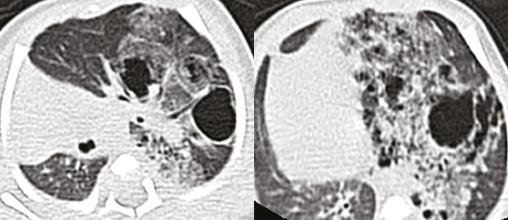

La radiographie pulmonaire objective une hyperclarté avasculaire de l’hémichamp pulmonaire gauche (fig. 1).